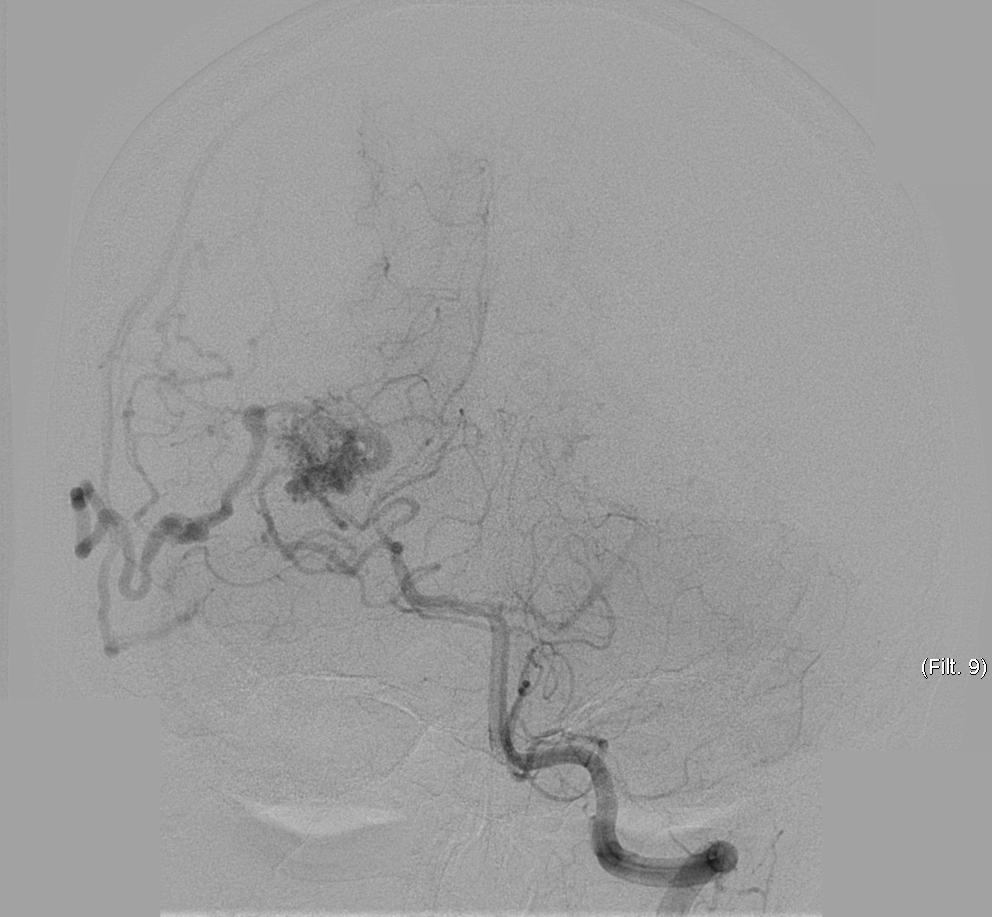

We chose FastICA to define the unmixing function and applied it on 19 DSA image series of subjects with an AVM. The series were composed of 12 to 38 images showing the malformations at different time points and were acquired at a low frame rate of 1.5fps to 6fps. As shown in Figure 2, the function was capable of decomposing the phases of vascular flow. We also generated phase-constrained color-coded overlays for DSA image series through the combination of the recovered sources and vessel masks, leading to a visualization where contrast flow appears progressively and is classified as artery, nidus and capillary, or vein. An example of this visualization is shown in Figure 3.